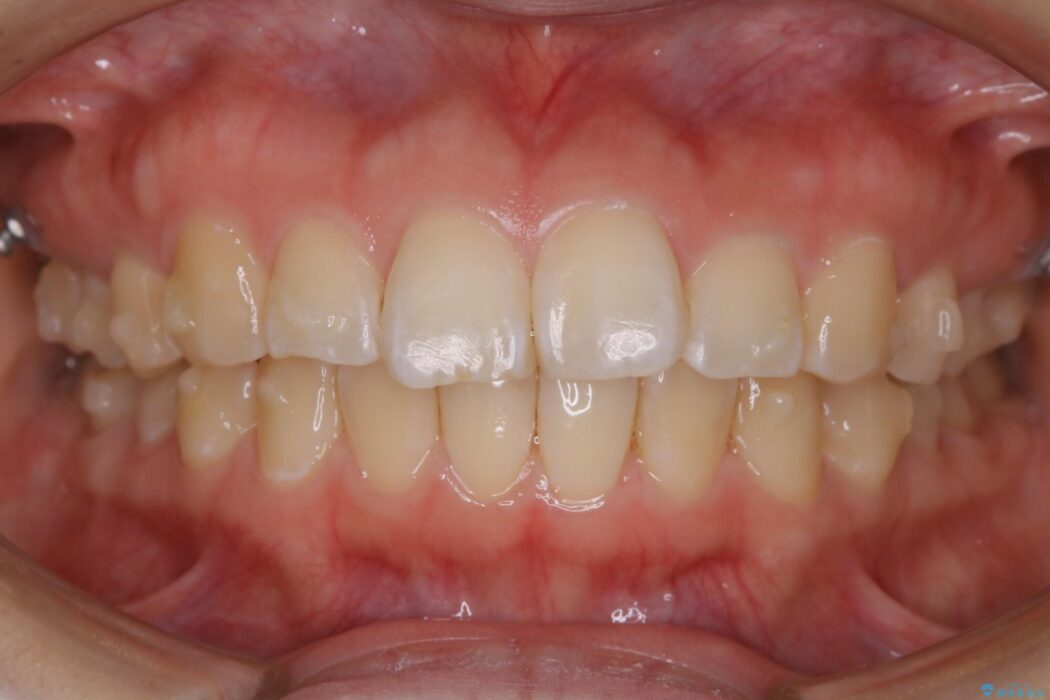

治療後について

咬合調整は咬合力を複数の歯に均等に分散することで歯の負担を少なくでき、歯の長持ちに繋がります。

噛み合わせが改善されたことによりしっかり噛めるようになったと喜んでいただきました。